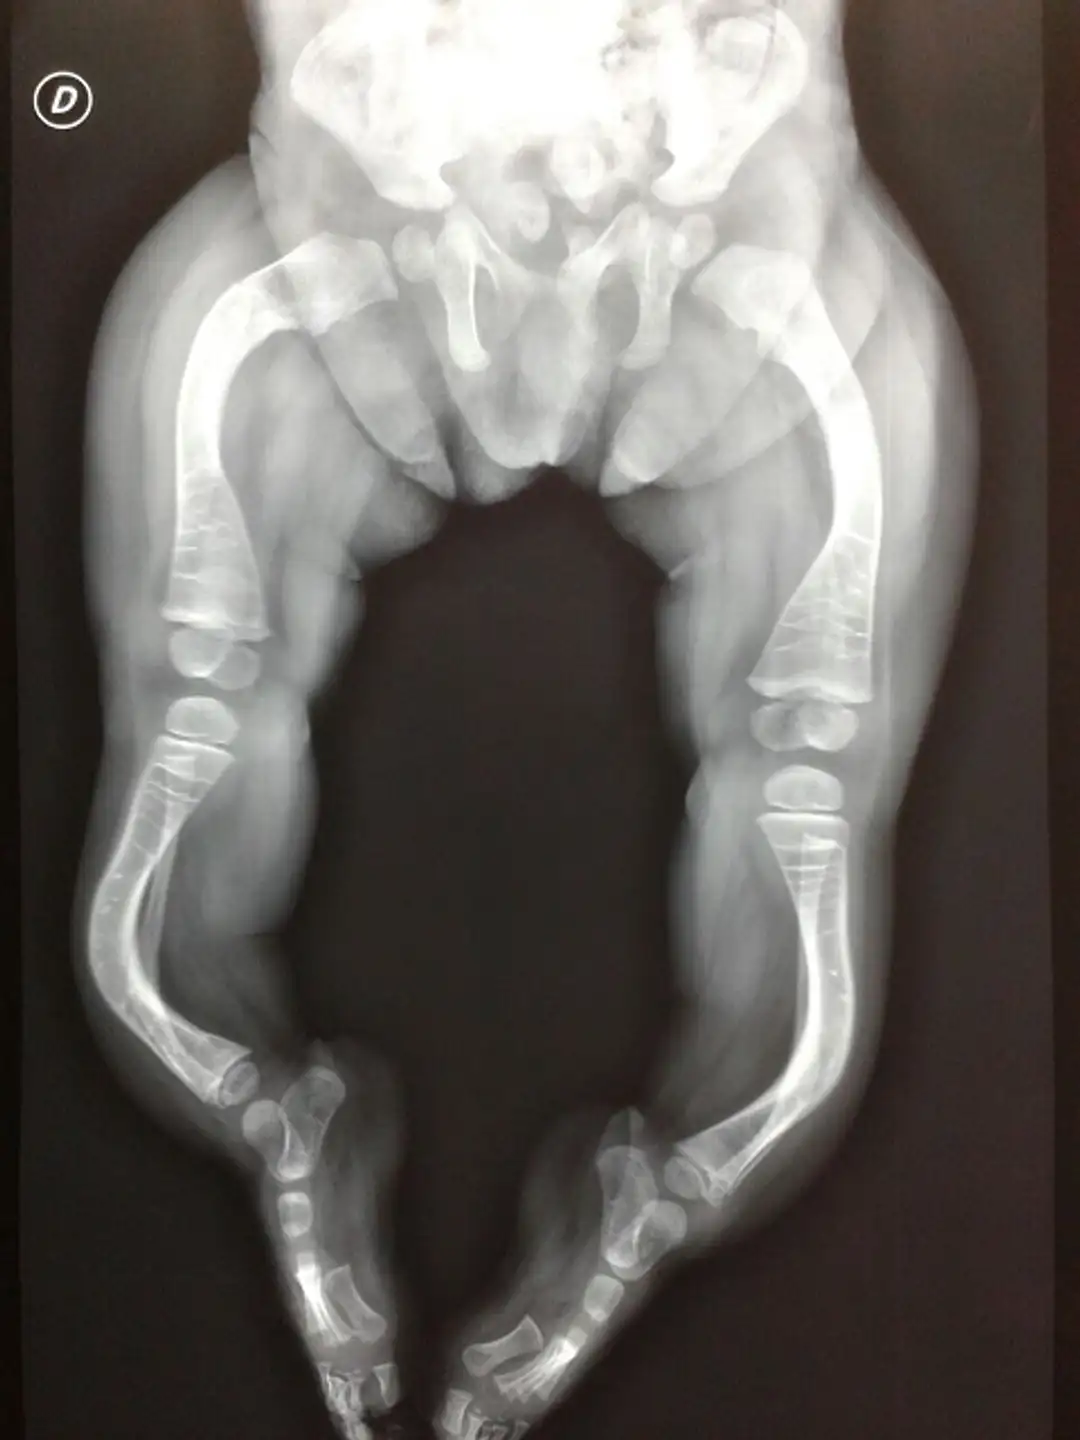

Tratamiento de la osteogénesis imperfecta, una patología poco frecuente.